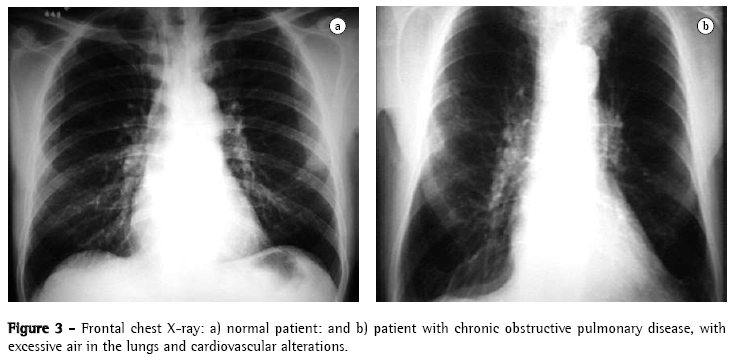

The yield of conventional chest X-ray in the evaluation of emphysema is quite limited. When there is no significant air trapping, the principal alteration is reduction of vasculature, which is only perceived too late in the natural history of the disease, and is an extremely subjective criterion. When there is air trapping (Figures 3 and 4), the criteria are safer, and can be divided into 3 basic groups of alterations,(6,8) presented in Chart 1. When all criteria are present, the diagnosis is definitively confirmed. It should be noted that the increased right chambers of the heart, with reduction of the intrasegmental vasculature, can also be identified in pulmonary arterial hypertension, without emphysema. It should also be noted that bullae are only present in approximately one-third of the cases.

Considering that the hemidiaphragm has a surface of approximately 250 cm2, we can calculate that each 4 cm dislocation of the diaphragm determines a dislocation equivalent to approximately 1 L of volume in each lung (2 L, if we consider both lungs). When there is air trapping, the mobility of the diaphragm is limited during expiration. End-expiratory pulmonary volume is significant in the recognition of emphysema. In general, the dislocation of the diaphragm between maximum inspiration and expiration ranges from 3 to 10 cm, corresponding to volumes ranging from 1500 mL to 5000 mL. Cranial dislocation <2 or 3 cm during expiration indicates limited diaphragmatic excursion in the individual with emphysema.(21)

The use of the height of the diaphragm as a diagnostic indicator is limited in various situations:

in patients with kyphoscoliosis;

in some individuals, such as athletes, who present a low diaphragm during inspirainspiration but preserve excellent mobility during expiration; and

in individuals with asthma, especially older children and adolescents, in whom the diaphragm can present some of the characteristics similar to those of the diaphragm of the individual with emphysema. However, cardiovascular alterations are not present.

In the three situations, diaphragmatic excursion should be greater than that of the individual with emphysema.